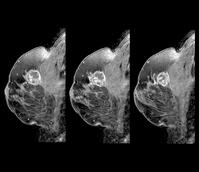

• °»³â±â ¿©¼º ºñ¸¸ÇÏ¸é ¡®Ä¡¹Ð À¯¹æ¡¯ °¨¼ÒÇÏÁö¸¸¡¦

°»³â±â ¿©¼º ºñ¸¸ÇÏ¸é ¡®Ä¡¹Ð À¯¹æ¡¯ °¨¼ÒÇÏÁö¸¸¡¦

°»³â±â ¿©¼ºÀÌ ºñ¸¸Çϸé Ä¡¹Ð À¯¹æÀÌ °¨¼ÒÇÑ´Ù´Â ¿¬±¸°¡ ³ª¿Ô´Ù.Ä¡¹Ð À¯¹æÀ̶õ À¯¹æ¿¡ Áö¹æ Á¶Á÷ÀÌ Àû°í À¯¼± Á¶Á÷ÀÇ ¾çÀÌ ¸¹Àº »óÅÂ. Ä¡¹Ð À¯¹æÀÎ °æ¿ì ¹æ»ç¼± Åõ°ú°¡ ¾î·Á¿ö À¯¹æ ¿¢½º·¹ÀÌ ÃÔ¿µ ½Ã ¾ÏÀ» ã¾Æ³»´Â µ¥ ¾î·Á¿òÀÌ ÀÖ´Ù. Ä¡¹Ð À¯¹æ ±× ÀÚü°¡ À¯¹æ¾ÏÀÇ ¿øÀÎ..